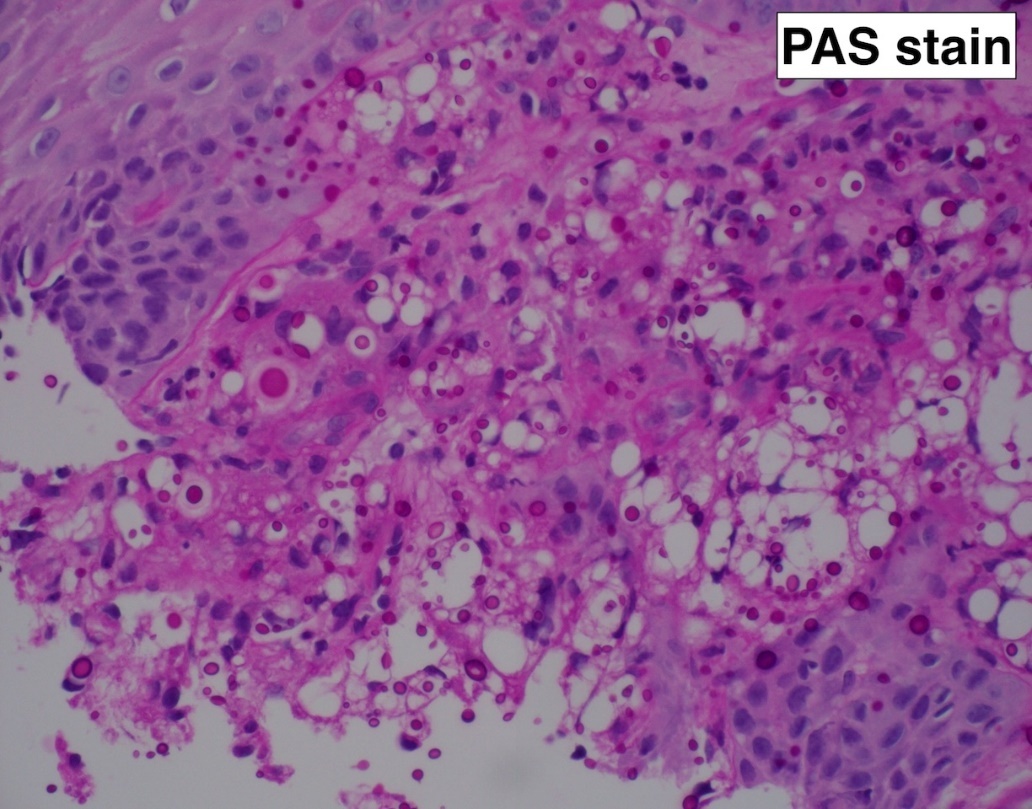

Introduction: Cryptococcus is an opportunistic fungal infection that primarily affects those with advanced HIV/AIDS. Oral manifestations are rare, and involvement of the tongue is exceptionally uncommon. Here, we present a rare case of lingual cryptococcosis.

Clinical Presentation: A 30-year-old male undergoing treatment for cryptococcal meningitis presented with a papillary-like mass on the tongue. Given his history of advanced HIV and former smoking, oral malignancy or infection was initially considered. A subsequent biopsy of the tongue nodule collected firm tan soft tissue fragments.

Results: Histologic evaluation of the mass on H&E staining revealed squamous epithelium with subepithelial tissue containing round to oval yeasts with thick mucoid capsules, amidst mild inflammation. Focal ulceration and bacterial colonies were present on the epithelial surface. No evidence of malignancy can be identified. Periodic Acid-Schiff (PAS) and Grocott Methenamine Silver (GMS) stains highlighted abundant fungal organisms. Mucicarmine decorated the highly characteristic gelatinous capsules with bright pink color, consistent with cryptococcosis.

Conclusion: This rare case of disseminated cryptococcosis involving the tongue in an HIV-positive patient highlights the need to consider fungal infections in atypical oral lesions. Oral cryptococcosis is uncommon and can easily be mistaken for more common conditions, such as neoplasms or bacterial infections. Our findings underscore the importance of considering fungal infections in the differential diagnosis of atypical oral lesions in immunocompromised patients, and reinforce the role of biopsy in guiding timely diagnosis and management.